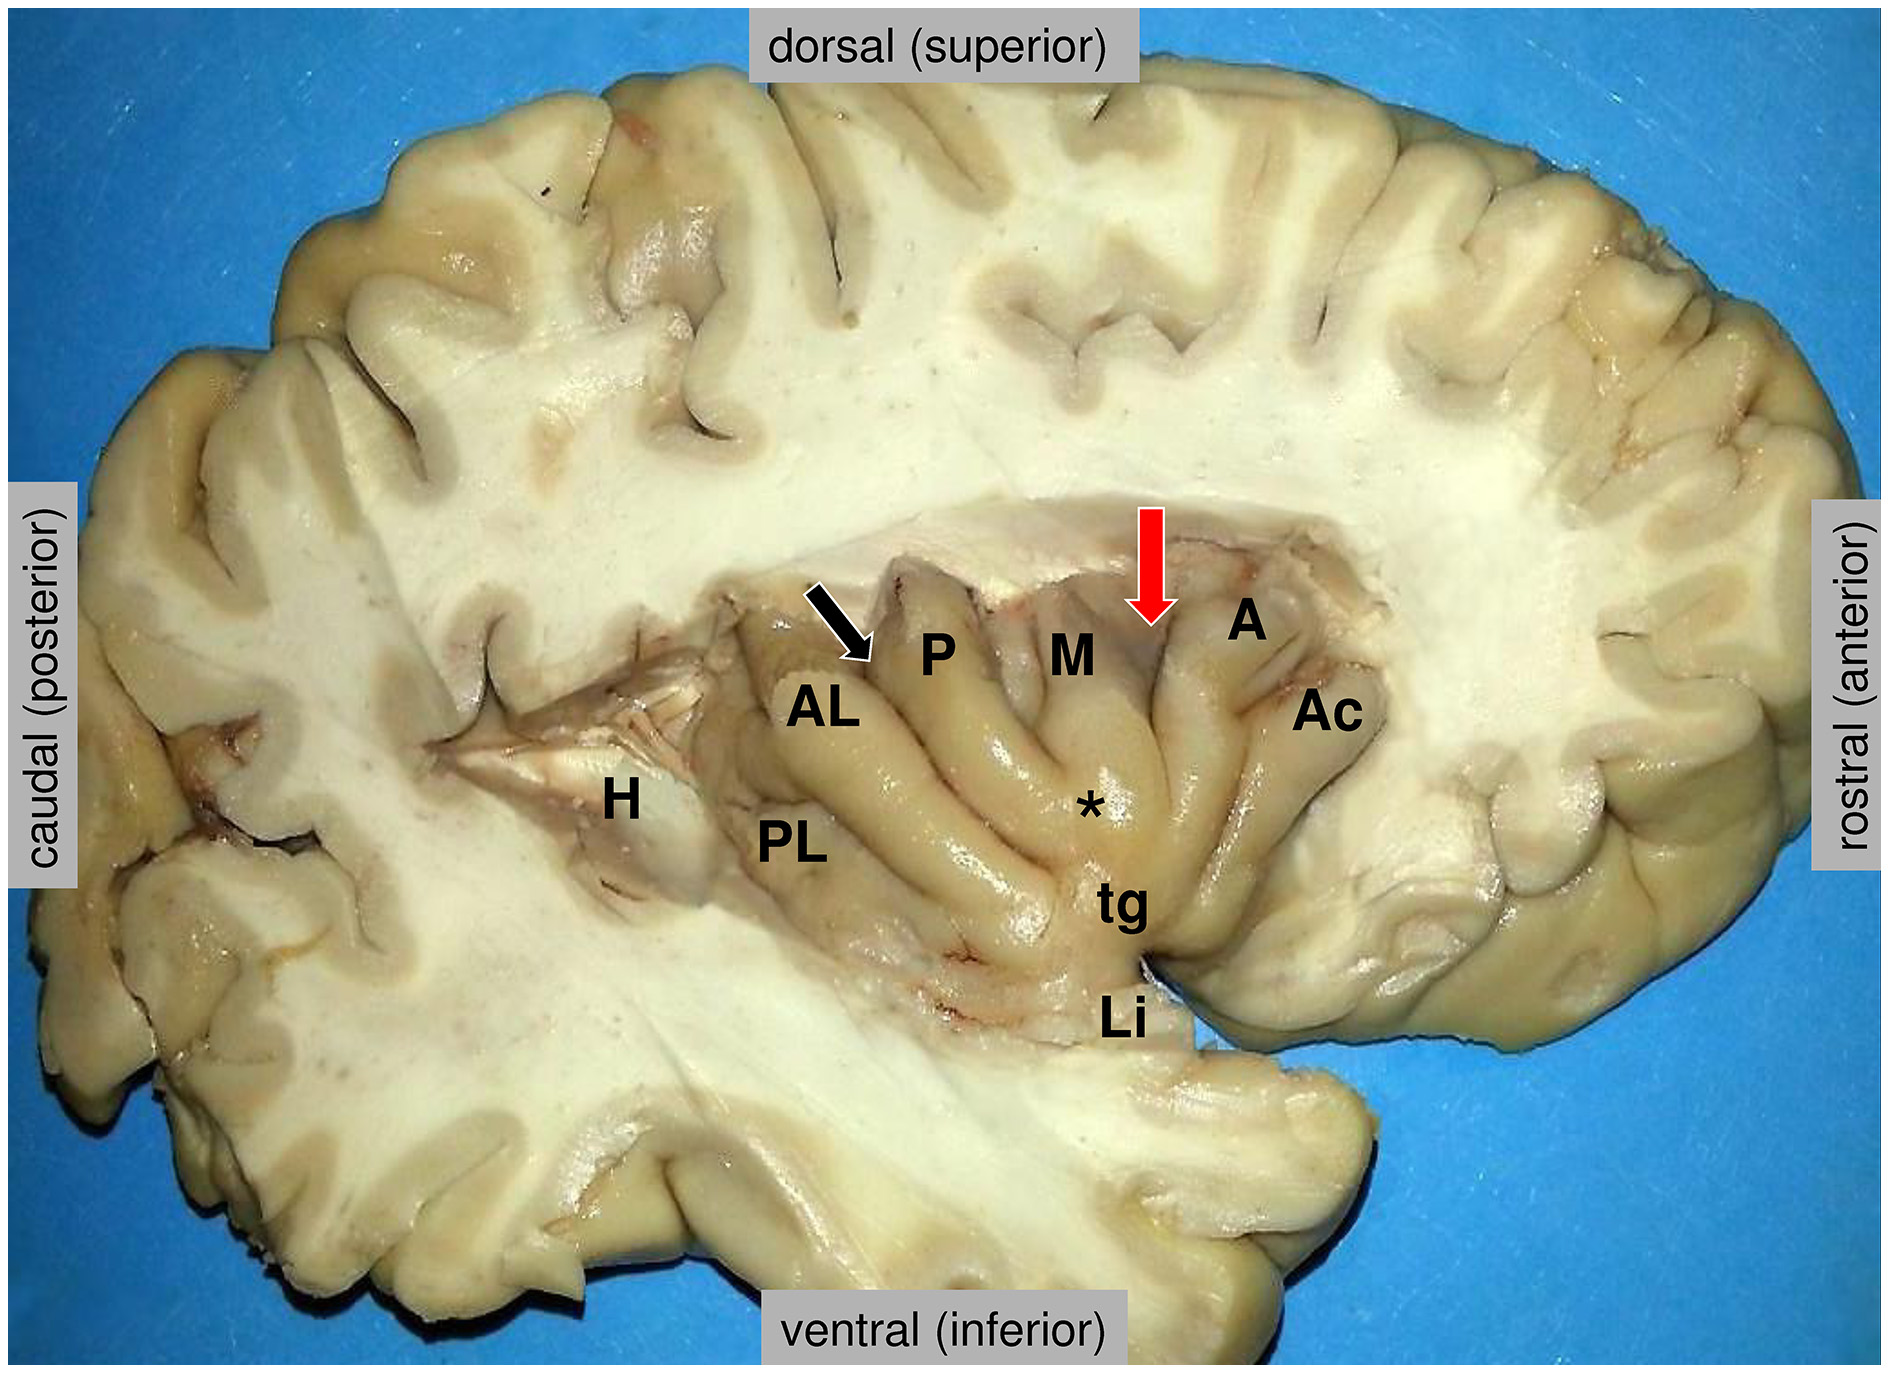

Coinciding with its wide connections in many different networks, the insula is implicated in a large number of different brain functions (Augustine, 1996; Craig, 2009b; Nieuwenhuys, 2012). According to a functional meta-analysis, they can be grouped into four functional domains (Kurth et al., 2010), defined as (1) a social-emotional domain (anterior-ventral insula) for emotion and empathy, (2) a cognitive domain for attention, speech production and language, (3) an olfacto-gustatory domain and (4) a sensorimotor domain including interoception, somatosensation, pain and motion. All these categories, except somatosensation and motion, show a remarkable overlap on the anterior-dorsal insula, precisely located at the dorsal end of the sulcus between the middle and anterior short gyri (Kurth et al., 2010; Figure 2, red arrow). Another meta-analysis identified the same main subdivisions, with posterior, ventro-anterior and dorso-anterior regions, corresponding to sensorimotor, affective/chemosensory, and cognitive processing, respectively (Chang et al., 2013). In a large sample of 355 participants, the persistent concordance between structural, functional, and connectivity-based parcellation of both (left and right) insular cortices was demonstrated (Kelly et al., 2012).

Figure 2. Anatomy of the insula, as disclosed in the depth of the lateral fissure. H = the posterior medial stub of the transverse temporal gyrus of Heschl (primary auditory cortex) that was resected to uncover the posterior long insular gyrus. The central sulcus (black arrow) divides the lateral surface of the insula into a small posterior insular lobule, composed of the anterior long (AL) and posterior long (PL) insular gyri that converge to the limen insulae (Li), and a large anterior insular lobule, composed of the anterior short (A), the middle short (M) and the posterior short (P) insular gyri that converge to the apex of the insula (*). The anterior face of the insula displays a variably present accessory insular gyrus (Ac) and a constant transverse insular gyrus (tg) that connects with the orbital surface of the frontal lobe. The red arrow marks the sulcus between the anterior short and middle short gyri, where the functional “overlap region” was found by Kurth et al. (2010). Figure courtesy of Drs. Thomas P. Naidich and Mary E. Fowkes, the Icahn School of Medicine at Mt. Sinai, New York.